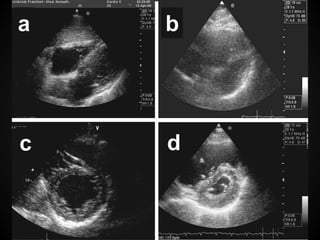

GLOBAL HEART FUNCTION

AND VENTRICULAR SIZE

Visual estimations of cardiac function are

equivalent to more detailed measurements,

decreased LV function can be diagnosed

by novice providers with minimal training.

For the non-cardiologist, one only needs to

be able to detect if there is a decrease in

global cardiac activity.

The American Society of Echocardiography

current recommendation to assess LV

function on the short-axis view at the level

of the mitral valve.

Assessment of global cardiac function:

– the inward motion of the endocardium

– the presence of thickening of the myocardium

– the longitudinal motion of the mitral annulus

– the overall geometry of the ventricle

In hypotensive patients, evaluation of the

function and the size of the RV can be

very useful in diagnosis and treatment for

pulmonary embolism.

RV enlargement in the presence of a

massive pulmonary embolus is predictive

of poor outcome.